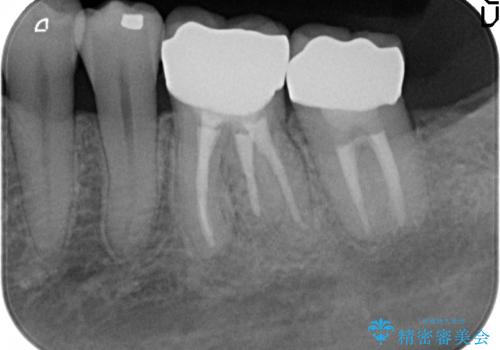

- 左下の奥歯が激しく痛むので診て欲しいといらっしゃった方の症例です。

左下7番目の歯に根尖病変を認めたため、再根管治療を行いました。

症状の消失を確認後、オールセラミッククラウンによる補綴を行いました。